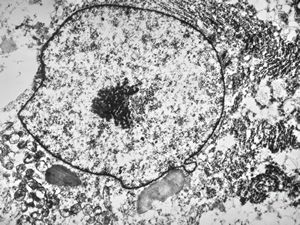

M,3y. | globoid leukodystrophy of Krabbe - n.suralis